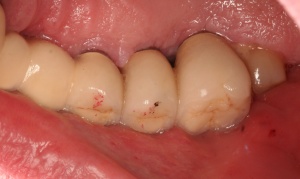

In der prächirurgischen Phase muss ein besonderes Augenmerk auf die prognostische Einschätzung der parodontalen und dentalen Situation gelegt werden. Dabei ist insbesondere auf die allgemeinmedizinische und spezielle dentale Anamnese zu achten. Bornstein et al. (2009) untersuchten den Einfluss von Allgemeinerkrankungen auf die Periimplantitis. Unter anderem Safi et al. (2009) wiesen auf die Bedeutung einer Parodontitishistorie hin. Aber auch die Lebensgewohnheiten des Patienten haben einen entscheidenden Einfluss (Tabakkonsum, ungenügende Mundhygiene, fehlende Nachsorge [Heitz – Mayfield & Huynh – Ba 2009]) (Abb. 3).

Diagnostische Parameter für die Beurteilung der dentalen und der periimplantären Zustände sind die Plaqueakkumulation, die Sondierungstiefen des Zahnes und des Implantates, Bluten auf Sondierung, Suppuration und der radiographische Knochenverlust (Salvi & Lang 2004). Unabdingbar ist im Minimum eine Sechspunktmessung (Sondiertiefen und klinischer Attachmentlevel). Immer wieder hört man von der Befürchtung, dass durch ein Sondieren des Implantates dieses geschädigt wird. In einer histomorphometrischen Studie an Hunden haben Etter et al. (2002) die Heilung des periimplantären Weichgewebes nach standardisiert klinischem Sondieren untersucht. Die Heilung des Epithelansatzes nach Sondierung des gesunden periimplantären Gewebes ist nach fünf Tagen abgeschlossen. Erfahrungsgemäß ist bei besonders aufmerksamem und vorsichtigem Sondieren ein äußerst geringes Verletzungsrisiko gegeben. Auch diese Techniken können in einem Praktikum bei einem Parodontologen aufgefrischt werden.